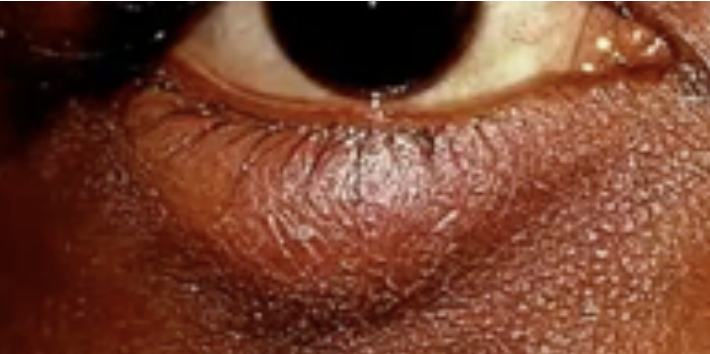

Blepharitis

Abnormalities of the External Eye

Staphylococcal infection of the eyelid

Seborrhea or Blepharitis

Abnormal Findings for 5. Redness, swelling, discharge, or lesions

Redness and crusting along the lid margins

Infection caused by Staphylococcus Aureus